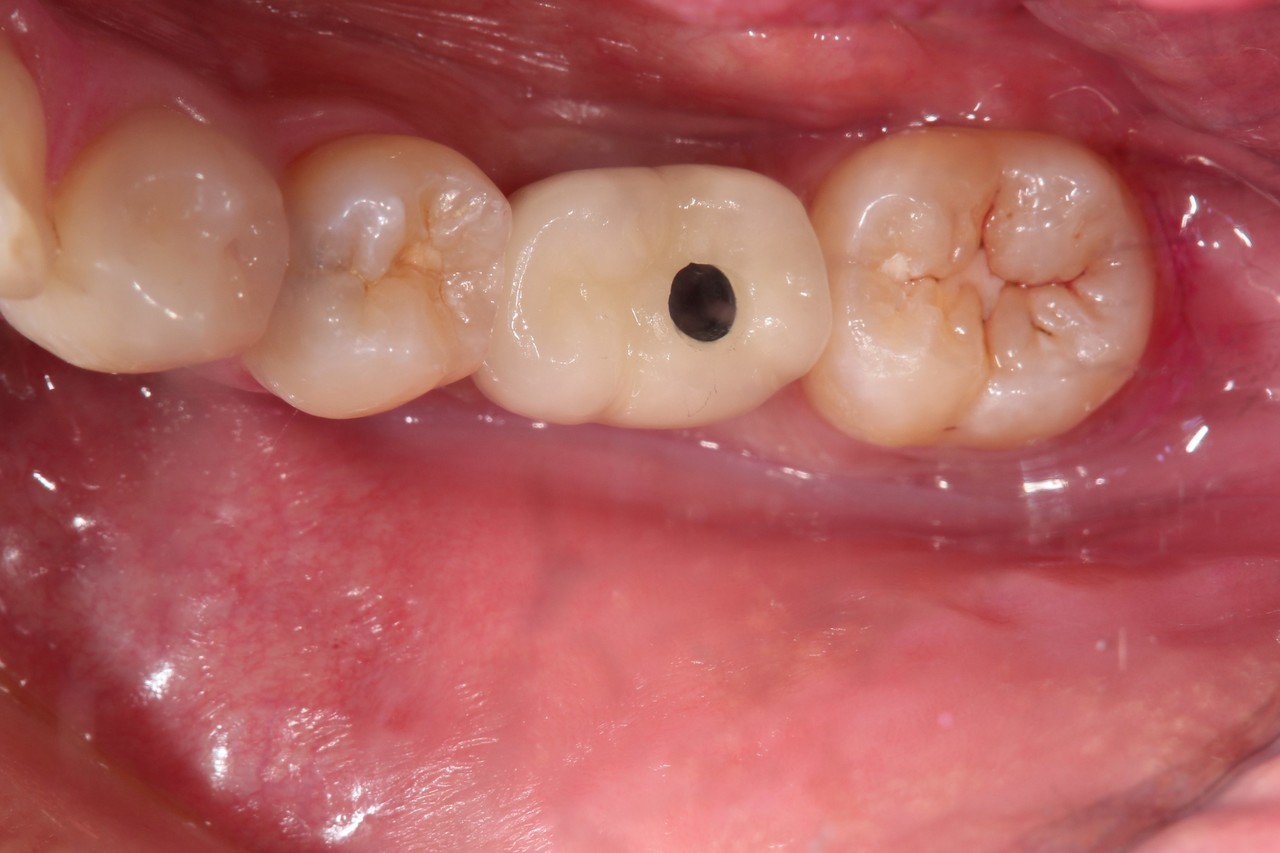

奥歯インプラント(スクリュー固定)

(伊東市 女性)

治療の流れ

むし歯で歯を失ってしまいました。

インプラントを埋入し、最終的な被せ物を装着しました。(ネジ穴をふさぐ前)

ネジ穴をふさぐとこの様な状態になります。

インプラント手術:250,000円

静脈内鎮静法:0円

既製アバットメント:90,000円

メタルボンド:130,000円

総額:470,000円+税